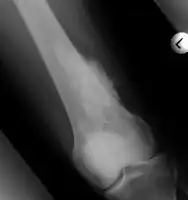

Medical imaging usually shows a well-defined wide-based bony growth on the surface of bone.[5] It can be pedunculated and irregular, giving it a "bizarre" appearance, and is not connected to underlying bone.[2]

X-ray left foot: Bizarre parosteal osteochondromatous proliferation in 2nd toe